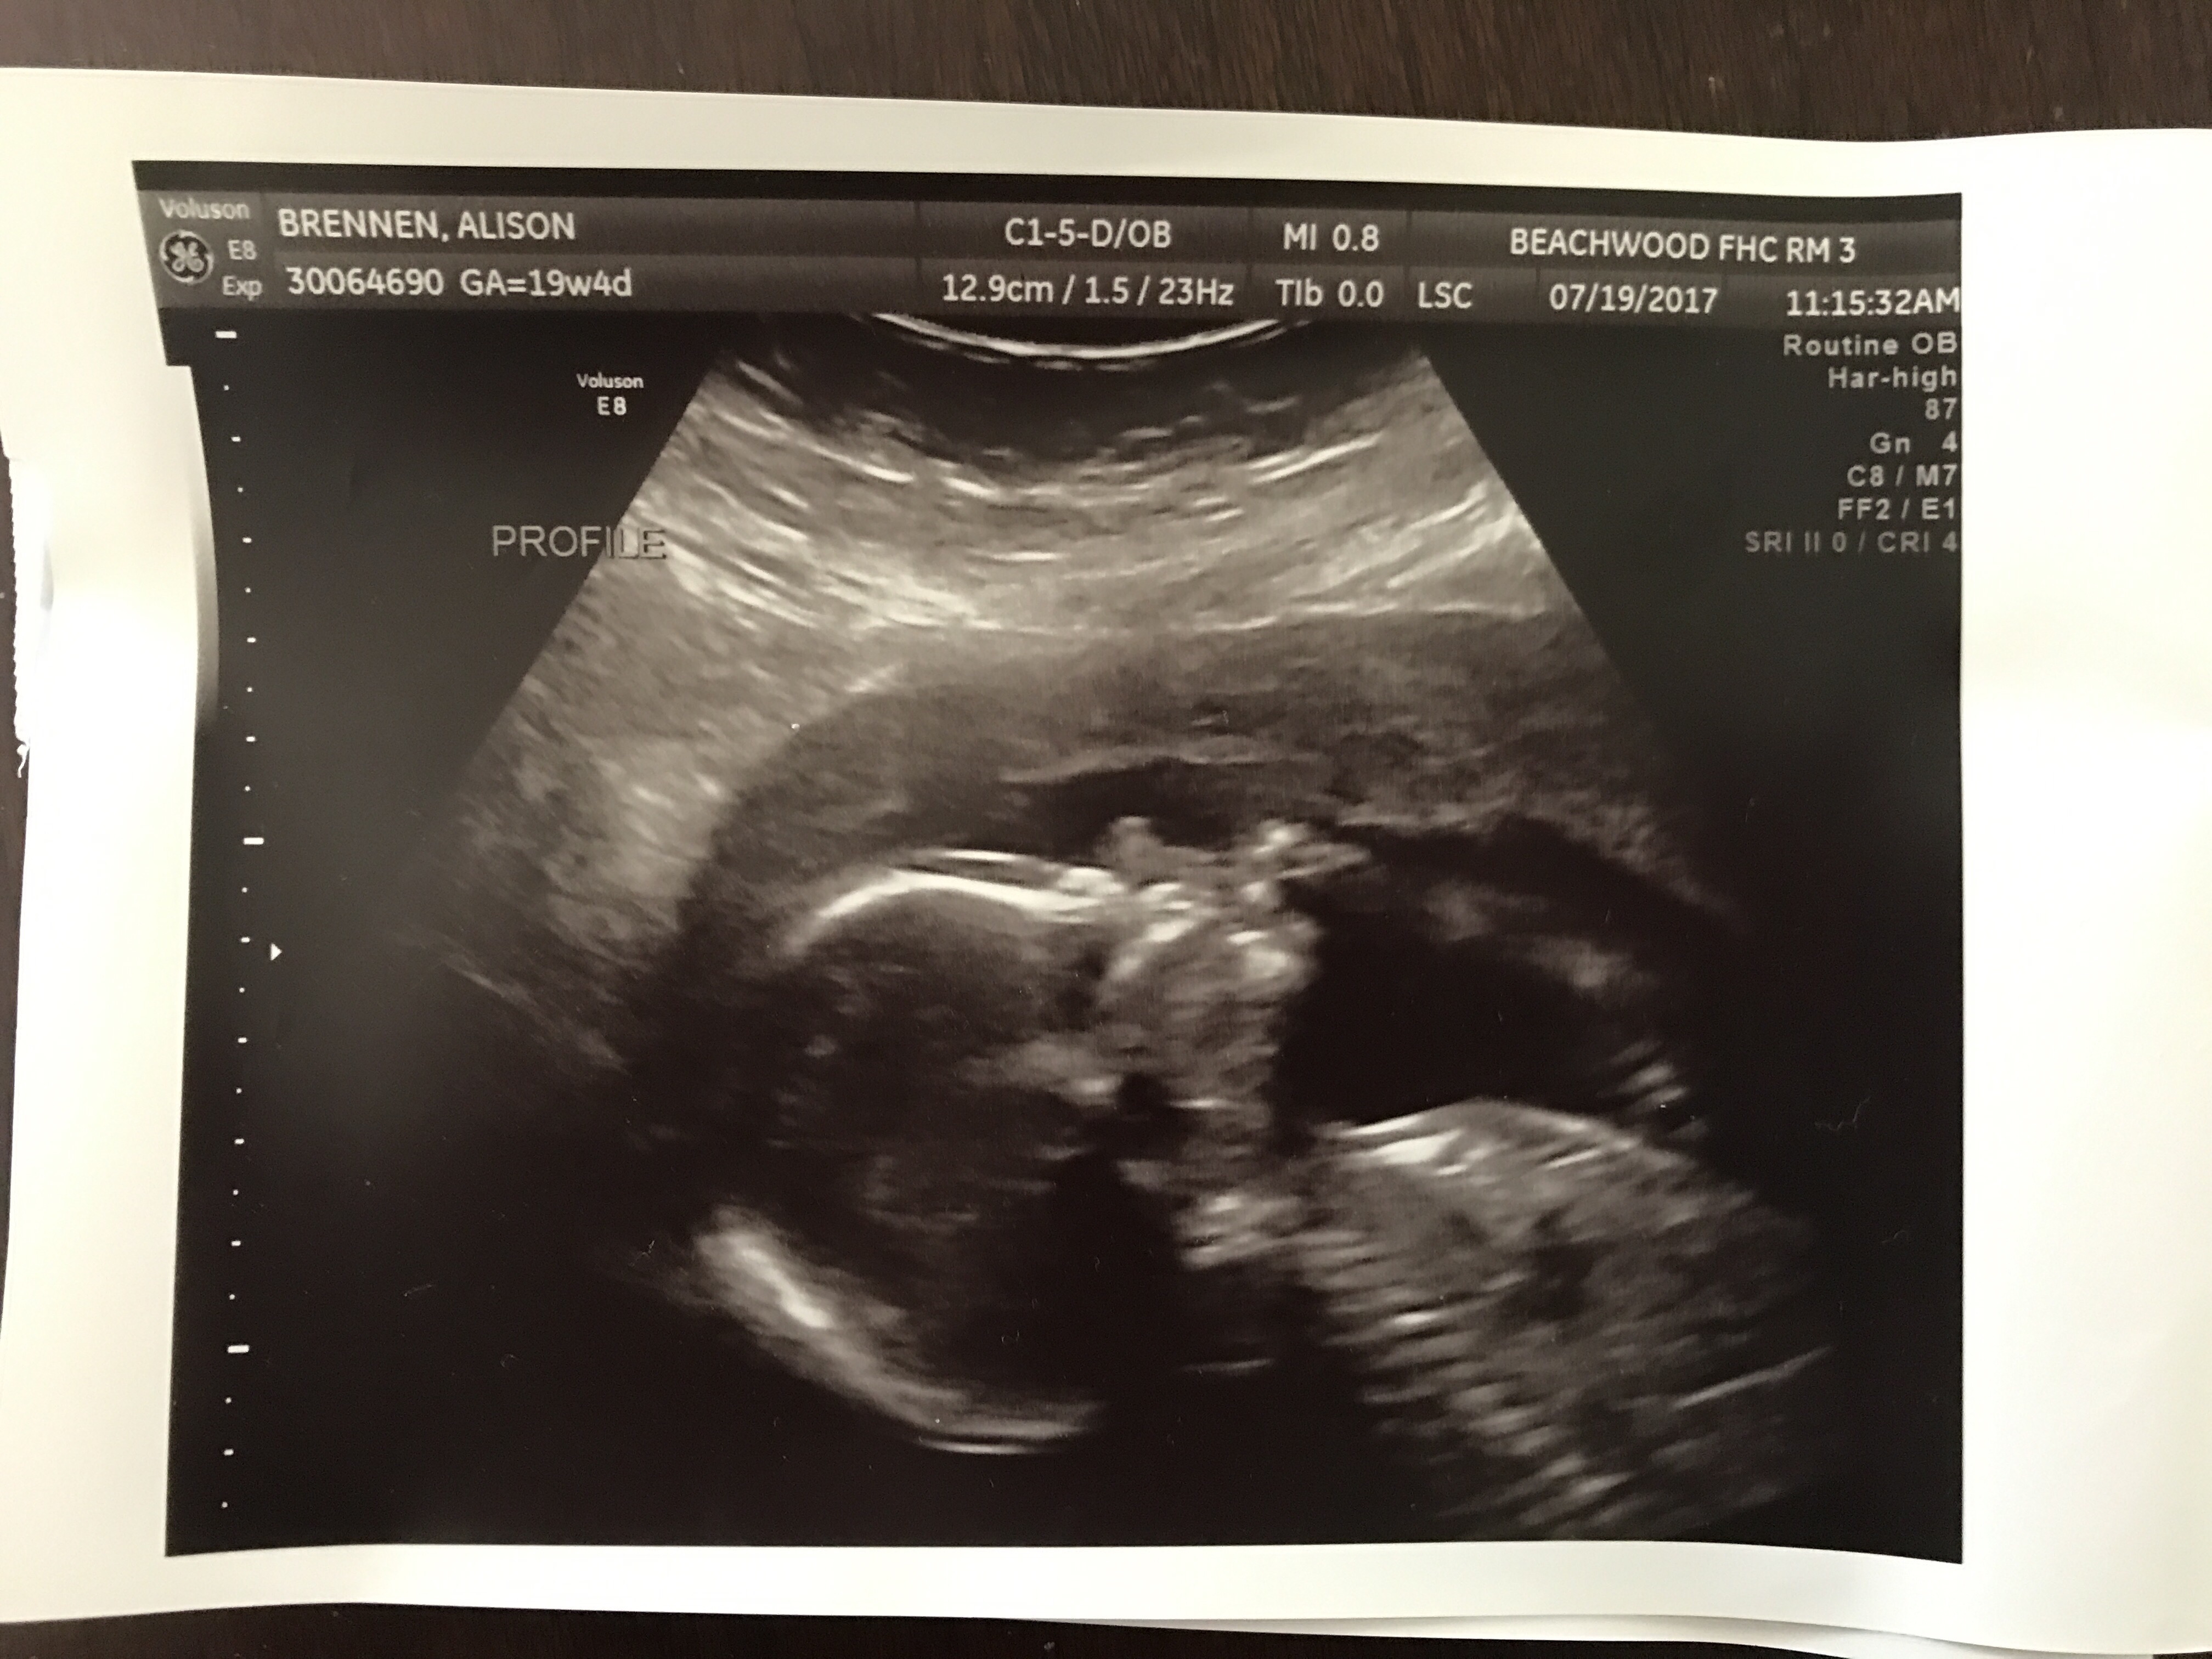

On Tuesday, we had our anatomy ultrasound and took Auntie Emmy and Grammy Ronda with us. The tech was not as intrigued as we were but we eventually wore her down and she started narrating what she was seeing. We were there for about twenty minutes so we got to see a lot – including our son’s beautiful face! (We also confirmed his gender, but I’ll save you – and him! – the pornography!) The tech and the doctor thought everything looked great – more wonderful news for us!

(Top: baby’s profile – he’s looking up; bottom: his little feet!)